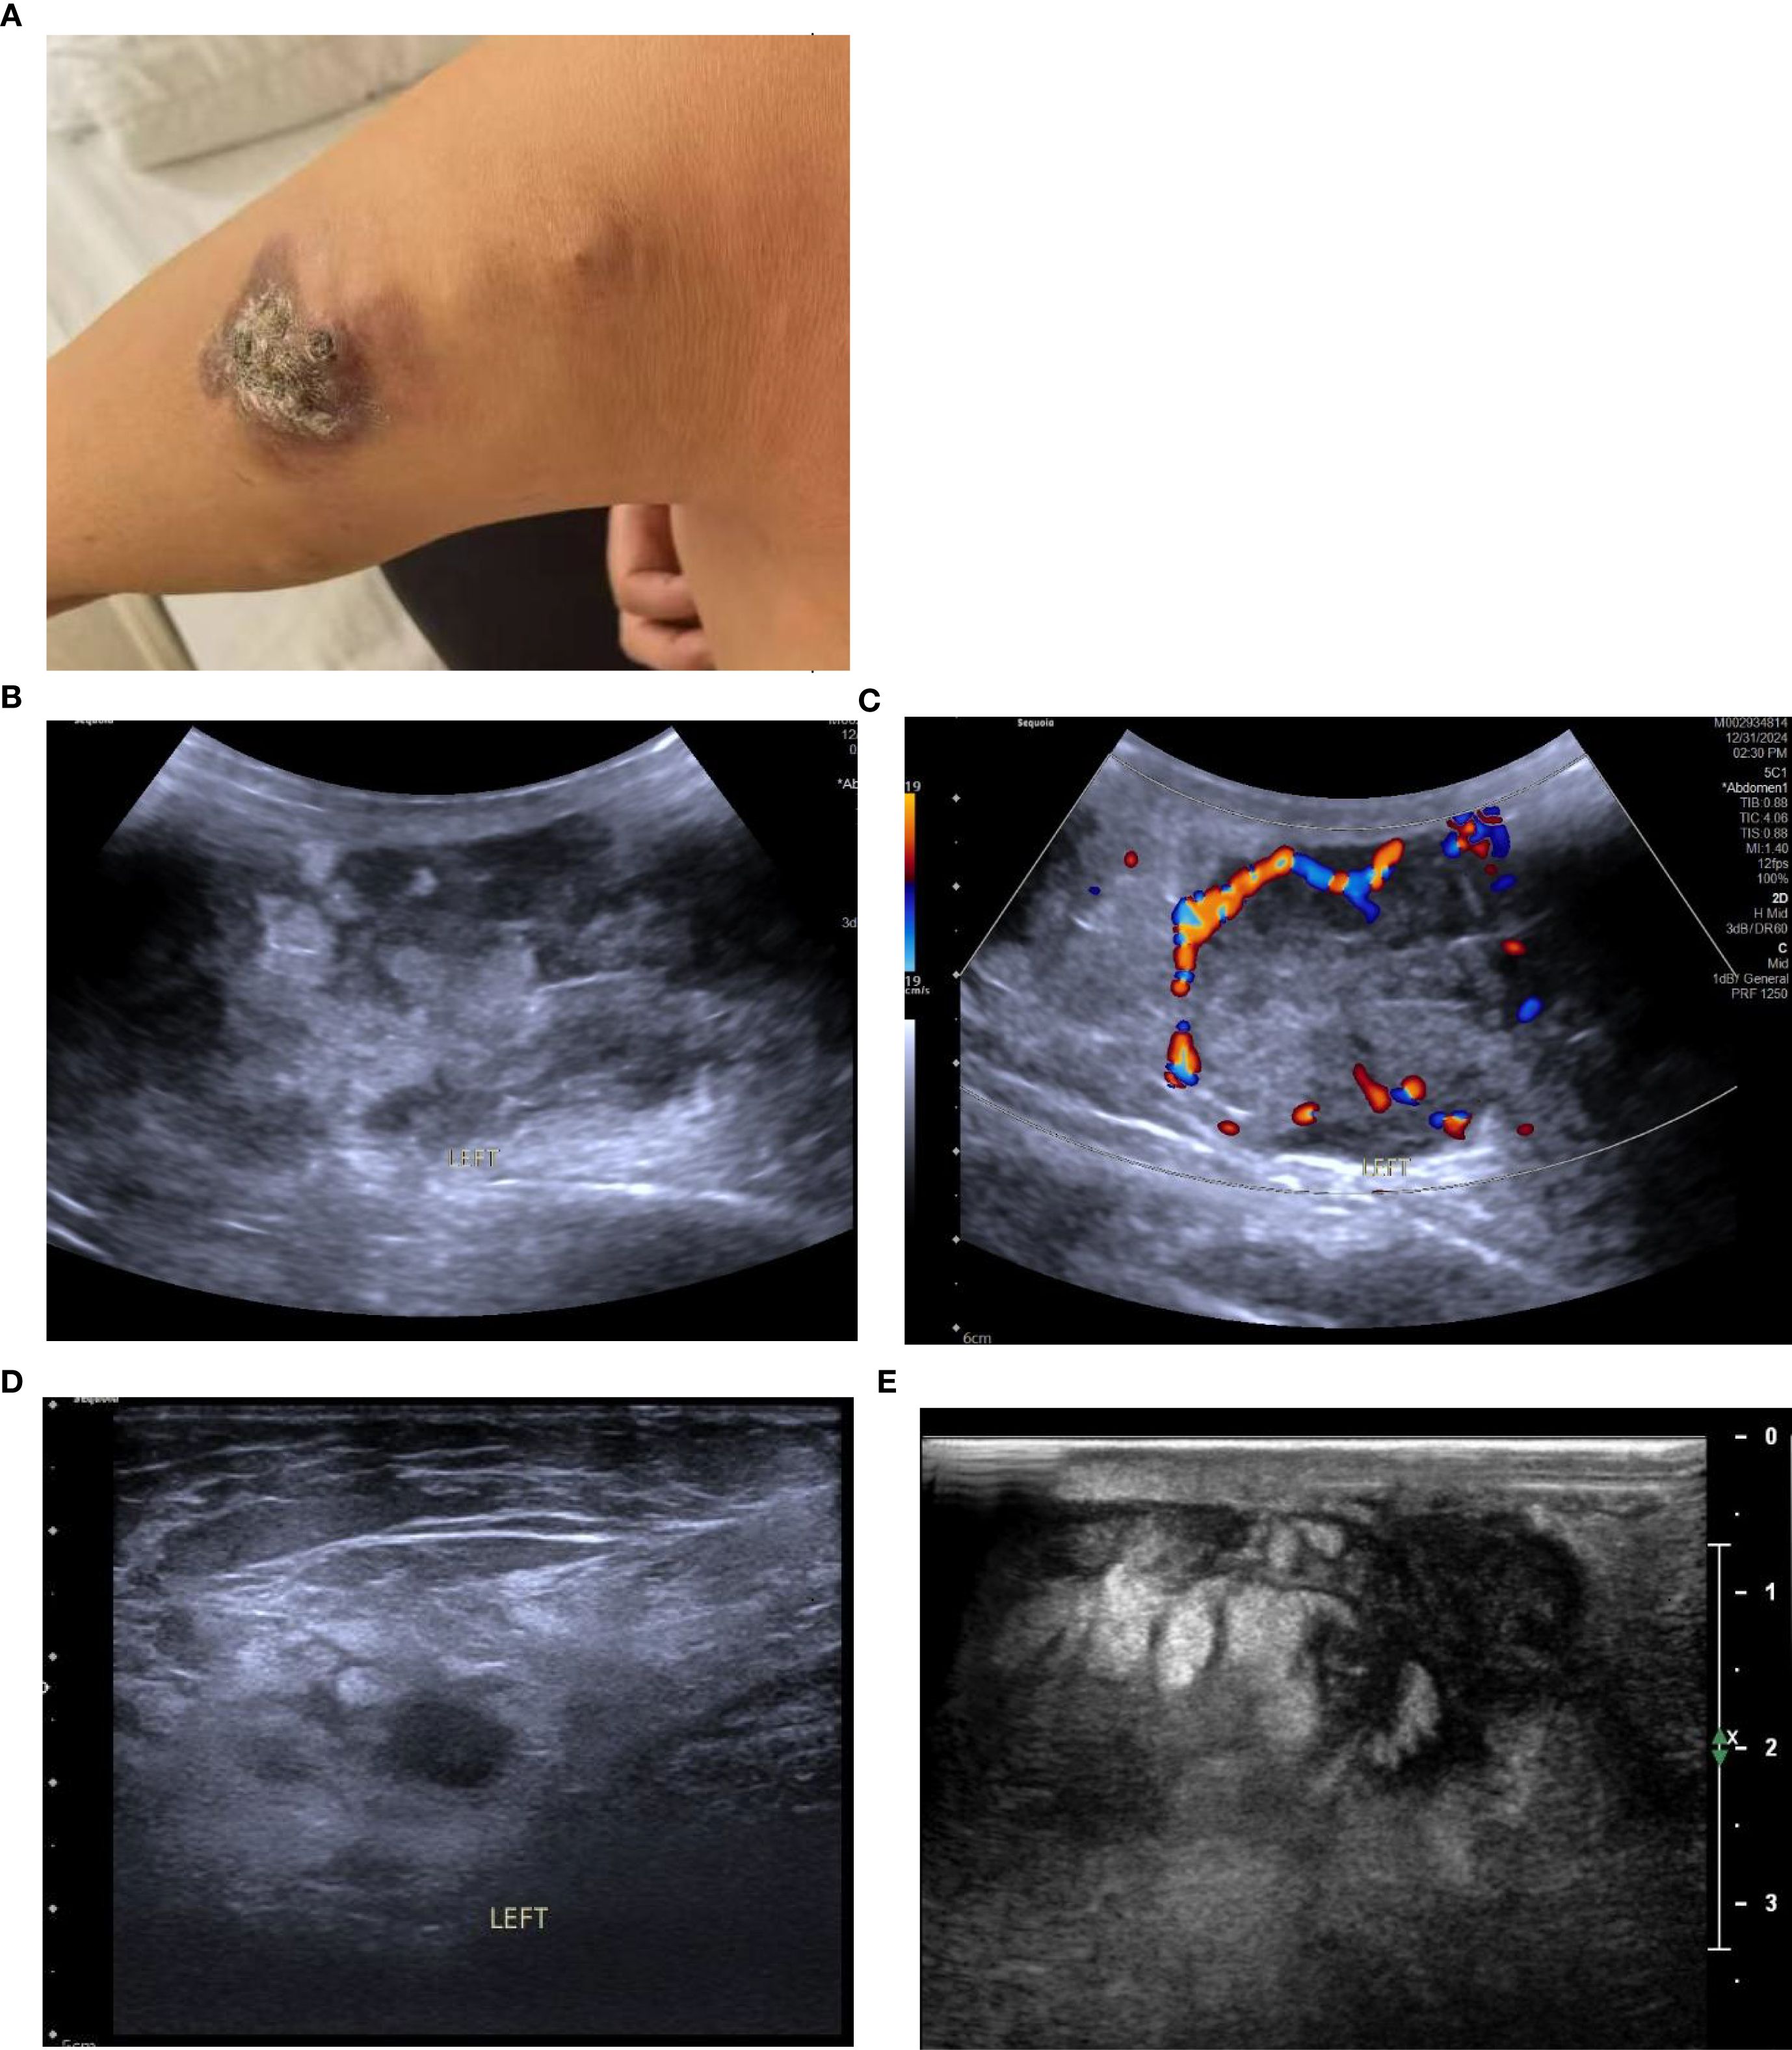

A 58-year-old female patient with no family history of breast cancer was found to have a left upper limb mass of about 2cm in size 30 years ago, which was not accompanied by redness, swelling and pain, so she did not pay attention to it and did not receive any treatment. During this period, the left upper extremity mass gradually increased to about 3 cm. In June 2024, the patient discovered a rapidly increasing mass in the left upper limb with a length of about 15cm, accompanied by pain, local redness, swelling, and ulceration. The patient sought medical attention at our hospital. Physical examination showed a raised red mass of about 15 × 8cm in the left upper limb, with scabs on the surface, hard texture, unclear boundaries, irregular shape, and obvious tenderness. (Figure 1A). Ultrasound examination showed multiple solid hypoechoic masses under the skin of the left upper arm, with unclear boundaries, blurred edges, irregular shapes, and abundant blood flow signals visible inside (Figures 1B, C). No obvious space occupying lesions were observed in both breasts. Multiple lymph node enlargement can be seen in the left axilla, with larger ones measuring 1.0 × 0.7cm in size, clear boundaries, regular morphology, and no obvious lymph node structure (Figure 1D). Ultrasound indicates multiple solid masses in the left upper arm, suggesting malignancy. Multiple lymph node swelling in the left axilla, suspected of metastasis. Chest CT shows multiple solid nodules in both lungs, with a high possibility of metastasis. The patient’s whole-body bone imaging, abdominal ultrasound, clavicle area ultrasound, and head MRI did not show any other tumor lesions. On January 2, 2025, the patient underwent ultrasound-guided biopsy of the left upper limb mass and left axillary mass. The pathological results of the left upper limb mass biopsy, combined with immunohistochemical markers, were consistent with ectopic breast tissue, with some areas being adenoma and others showing malignant transformation (metaplastic carcinoma). Immunohistochemistry results: ER (focal +), PR (focal weak +), HER-2 (0), Ki67 (approximately 80% +). PD-L1 CPS 80. The pathological results of the left axillary lymph node biopsy revealed malignant tumor, which was considered to be metastasis from the left upper limb malignant tumor (metaplastic carcinoma) (Figure 2).

Figure 1. (A) The patient had a protruding red mass on the left upper limb, with a crust on the surface, hard in texture, ill-defined margins, and an irregular shape. (B) Conventional ultrasound revealed multiple hypoechoic solid masses in the subcutaneous tissue of the left upper arm, with ill-defined margins, indistinct edges, and irregular shapes; the largest measures 8.2 × 3.4 cm. (C) CDFI showed relatively rich blood flow signals within the masses. (D) Enlarged lymph nodes were visible in the left axilla, with clear margins and no obvious lymph node structure. (E) After two cycles of chemotherapy, the largest mass measures approximately 4.0 × 2.6 cm (a marked reduction from its pre-treatment size).

Due to the patient’s refusal to undergo surgery, a combination of chemotherapy, radiotherapy, and endocrine therapy was used. Chemotherapy began on January 16, 2025. The specific medication was 200mg of albumin bound paclitaxel (Day 1 and Day 8) and 1.5g of capecitabine twice a day (Day 1 to Day 14), with a cycle of 21 days. The patient has completed two chemotherapy cycles and the left upper limb mass has shrunk compared to before (Figure 1E).